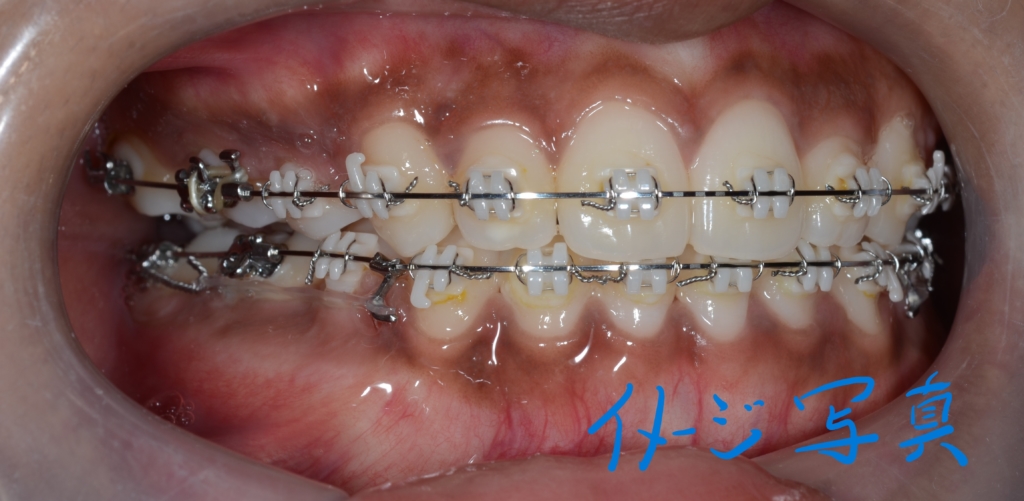

この方の写真が見つからないので、同じことをしている他の方の写真をイメージ写真としてあげています

この方の写真を探したのですが見つからないため、全く同じことをしている患者さんの写真を「イメージ写真」として代用しています。